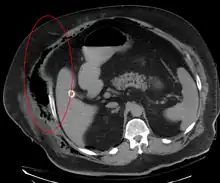

Necrotizing fasciitis producing gas in the soft tissues as seen on CT scan

Imaging has a limited role in the diagnosis of necrotizing fasciitis. The time delay in performing imaging is a major concern. Plain radiography may show subcutaneous emphysema (gas in the subcutaneous tissue), which is strongly suggestive of necrotizing changes, but it is not sensitive enough to detect all the cases, because necrotizing skin infections caused by bacteria other than clostridial infections usually do not show subcutaneous emphysema. If the diagnosis is still in doubt, computed tomography (CT) scans and magnetic resonance imaging (MRI) are more sensitive modalities than plain radiography. However, both the CT scan and MRI are not sensitive enough to rule out necrotizing changes completely.[2] CT scan may show fascial thickening, edema, subcutaneous gas, and abscess formation.[2] In MRI, when fluid collection with deep fascia involvement occurs, thickening or enhancement with contrast injection, necrotizing fasciitis should be strongly suspected. Meanwhile, ultrasonography can show superficial abscess formation, but is not sensitive enough to diagnose necrotizing fasciitis.[2] CT scan is able to detect about 80% of cases, while MRI may pick up slightly more.[14]